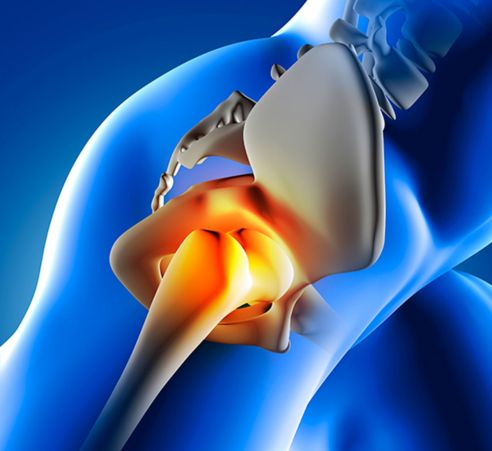

Bursite no Quadril Você já sentiu uma dor incômoda na lateral do quadril, que parece piorar ao caminhar, subir escadas ou, principalmente, ao tentar dormir deitado sobre esse lado? Essa dor, que pode irradiar pela coxa, é a queixa mais comum da bursite trocantérica, uma inflamação em uma das bursas do quadril. Embora o nome pareça complicado, o problema é bastante frequente e pode limitar consideravelmente sua qualidade de vida. Para entender a dor, imagine as bursas como pequenas bolsas cheias de líquido que funcionam como amortecedores, reduzindo o atrito entre os ossos, tendões e músculos perto das articulações. No quadril, existe uma bursa importante localizada logo acima do “trocanter maior”, que é aquela saliência óssea que sentimos na lateral da coxa. Quando essa bursa fica inflamada, surge a bursite trocantérica. A inflamação geralmente não tem uma causa única, mas sim um conjunto de fatores. O uso excessivo da articulação em atividades de repetição, como corrida ou caminhada intensa, é um gatilho comum. Além disso, fraqueza nos músculos do quadril e glúteos, lesões anteriores na região, e até mesmo uma diferença no comprimento das pernas podem sobrecarregar a bursa e levar ao quadro inflamatório, que é mais frequente em mulheres e pessoas de meia-idade. O diagnóstico correto é essencial para diferenciar a bursite de outros problemas no quadril, como a artrose. Ele é feito pelo ortopedista, primeiramente através de um exame físico detalhado, onde a palpação do local exato da dor é um indicativo importante. Exames de imagem, como o ultrassom ou a ressonância magnética, são frequentemente solicitados para confirmar a inflamação da bursa e avaliar o estado dos tendões próximos. A boa notícia é que o tratamento da bursite no quadril é, na grande maioria dos casos, conservador e muito eficaz. A abordagem inicial envolve repouso relativo das atividades que causam dor, aplicação de gelo na lateral do quadril e o uso de medicamentos anti-inflamatórios. A fisioterapia é fundamental, focando em exercícios de alongamento e, crucialmente, no fortalecimento da musculatura que estabiliza o quadril. Em casos onde a dor é mais intensa ou persistente, o médico pode optar por uma infiltração com corticoide diretamente na bursa, o que costuma trazer um alívio rápido da inflamação. A cirurgia é extremamente rara para essa condição. Não aceite conviver com a dor que atrapalha seu sono e seus movimentos; procure um especialista para um diagnóstico preciso e um tratamento que devolva seu bem-estar. Agendar Consulta